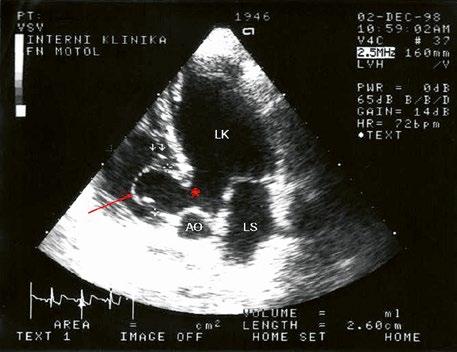

Obr. 45.32 Spontánní uzávěr velkého defektu komorového septa (*) velkým pseudoaneuryzmatem komorového septa (šipka), TTE, pětidutinová apikální projekce

AO – aorta, LK – levá komora, LS – levá síň, PK – pravá komora